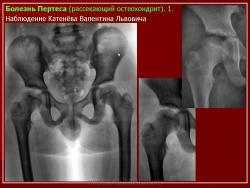

4. Частичные клиновидные некрозы суставных участков костей (так называемый рассекающий, отсекающий суставной край, или расслаивающий остеохондроз):

Остеохондропатия головки бедренной кости

(болезнь Легга-Кальве-Пертеса)

(Osteochondropathia caput femoris)

Остеохондропатия головки бедренной кости впервые была описана в 1909-1910 гг. независимо друг от друга Вальденстромом в Швеции, Леггом в США, Кальве во Франции и Пертесом в Германии.

Рентгенологическое обследование помогает в постановке диагноза. Для сравнительного анализа производят рентгеновские снимки обоих тазобедренных суставов, а также рентгенограмму в положении Лауэнштейна. Наиболее полную информацию о локализации и распространенности патологических изменений в головке бедра дает компьютерная и ядерно-магнитно-резонансная томография тазобедренных суставов. В ранней диагностике заболевания высокоэффективно радиоизотопное исследование (сцинтиграфия).

Изменения на рентгенограммах зависят от стадии процесса.

В I стадии (асептиче­ского некроза губчатой кости эпифиза и костного мозга) изменения отсутствуют либо незначительные: в виде остеопороза костей, образующих тазобедренный сустав, извилистости и неравномерности хрящевой эпифизарной пластинки, неоднородности и пятнистости шейки бедра, некоторого расширения щели сустава.

Во II стадии (импрессионного перелома) головка бедренной кости утрачивает характерную трабекулярную структуру, шейка бедра становится более остеопоротичной. Суставная щель отчетливо расширяется по сравнению со здоровым тазобедренным суставом. Эпифиз головки уплотняется, склерозируется и деформируется (вследствие сохраняющейся нагрузки).

В III стадии (фрагментации эпифиза) суставная щель по-прежнему расширена, головка сплющена и как бы разделена на отдельные глыбки или неправильной формы мелкоочаговые фрагменты. Обычно определяется от 2 до 5 таких фрагментов, а иногда и больше. Вертлужная впадина уплощается.

В IV стадии (репарации) определяется формирование новых костных балочек, эпифиз полностью замещается новообразованной костью с участками просветления в центре.

В V стадии (конечной) завершается структурная перестройка и восстановление формы головки и шейки бедра. Суставная щель суживается и приближается по своей величине к нормальной. Если лечение было правильным, форма восстановленной головки незначительно отличается от сферической; в противном случае формируется грибовидная головка с укороченной расширенной шейкой. При этом вертлужная впадина не полностью покрывает увеличенную деформированную головку, что впоследствии приводит к развитию вторичного коксартроза.